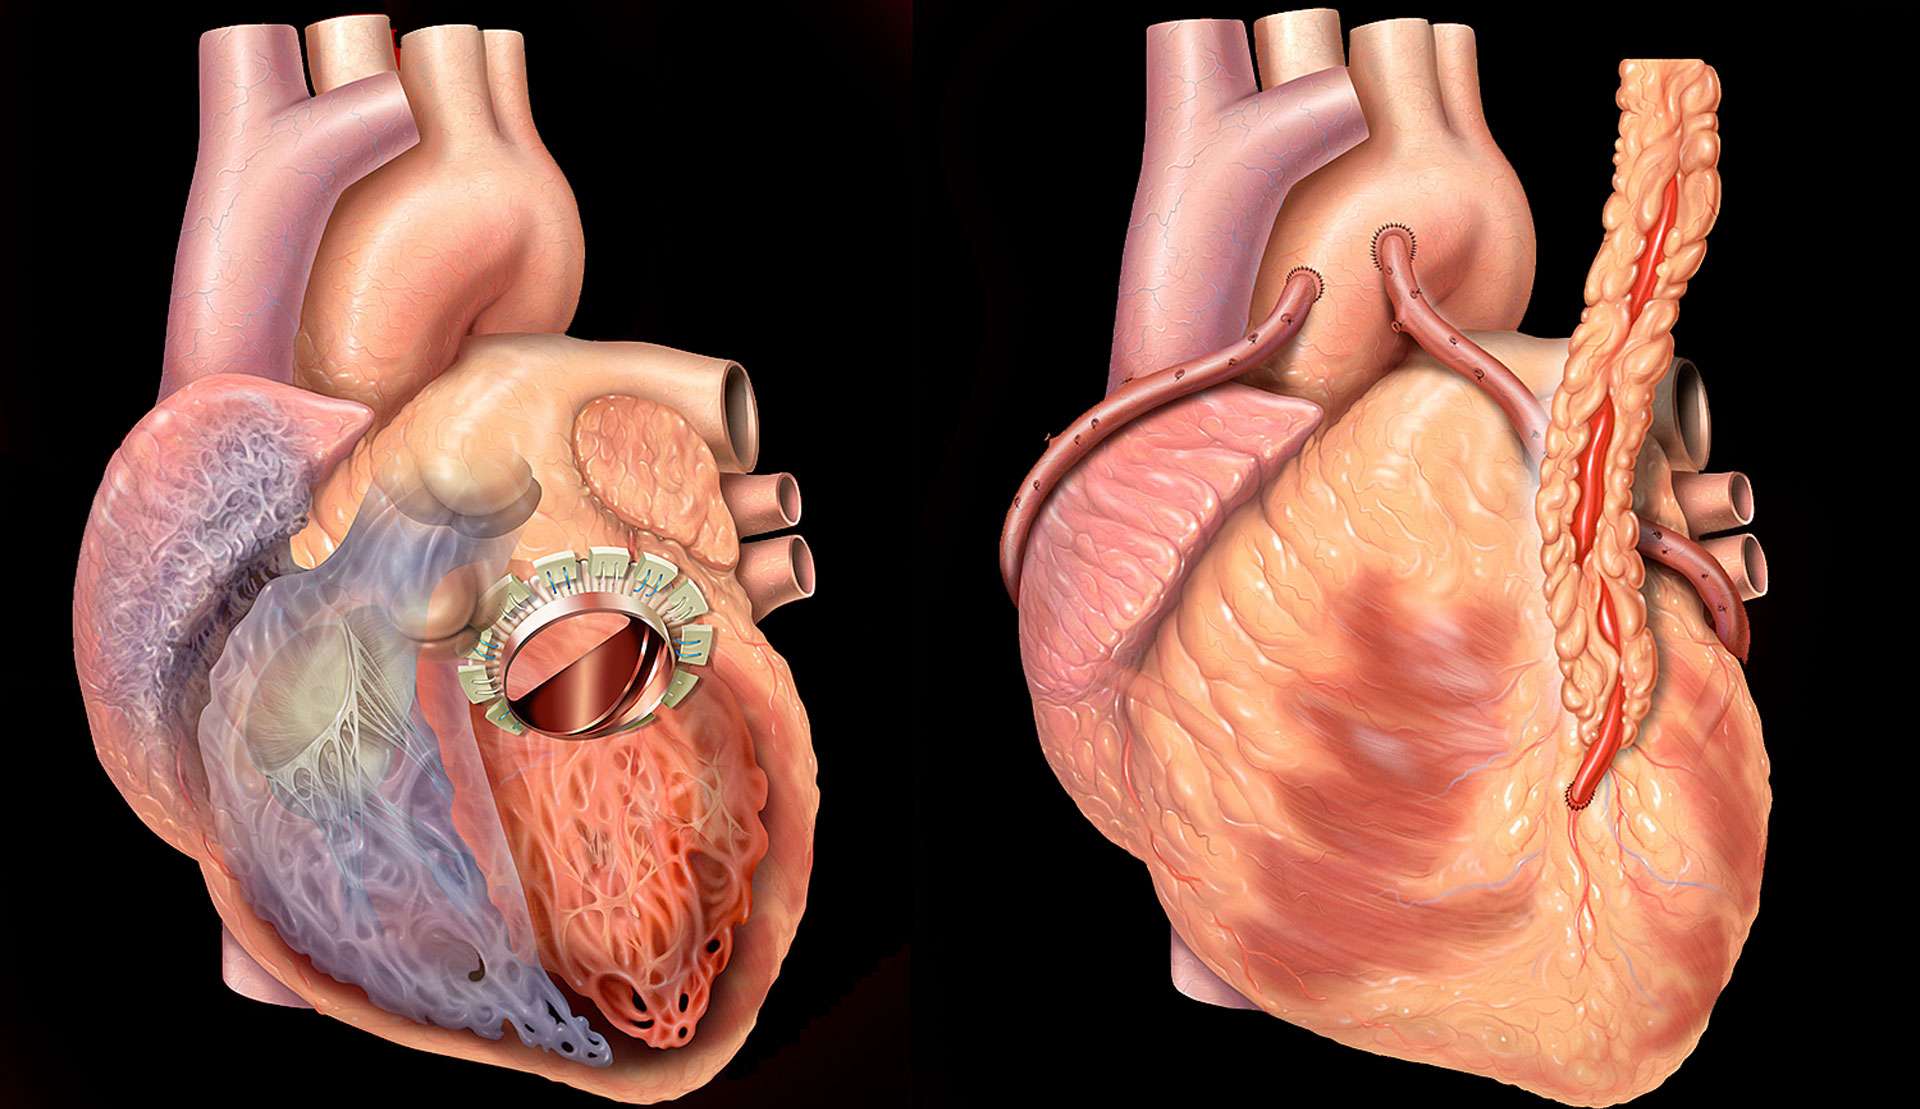

Фотографии и информация о приобретенных пороках сердца